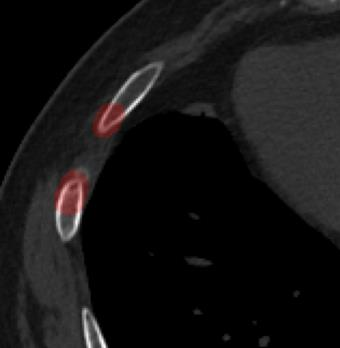

Rib fractures are a common and potentially severe injury that can be challenging and labor-intensive to detect in CT scans. While there have been efforts to address this field, the lack of large-scale annotated datasets and evaluation benchmarks has hindered the development and validation of deep learning algorithms. To address this issue, the RibFrac Challenge was introduced, providing a benchmark dataset of over 5,000 rib fractures from 660 CT scans, with voxel-level instance mask annotations and diagnosis labels for four clinical categories (buckle, nondisplaced, displaced, or segmental). The challenge includes two tracks: a detection (instance segmentation) track evaluated by an FROC-style metric and a classification track evaluated by an F1-style metric. During the MICCAI 2020 challenge period, 243 results were evaluated, and seven teams were invited to participate in the challenge summary. The analysis revealed that several top rib fracture detection solutions achieved performance comparable or even better than human experts. Nevertheless, the current rib fracture classification solutions are hardly clinically applicable, which can be an interesting area in the future. As an active benchmark and research resource, the data and online evaluation of the RibFrac Challenge are available at the challenge website. As an independent contribution, we have also extended our previous internal baseline by incorporating recent advancements in large-scale pretrained networks and point-based rib segmentation techniques. The resulting FracNet+ demonstrates competitive performance in rib fracture detection, which lays a foundation for further research and development in AI-assisted rib fracture detection and diagnosis.